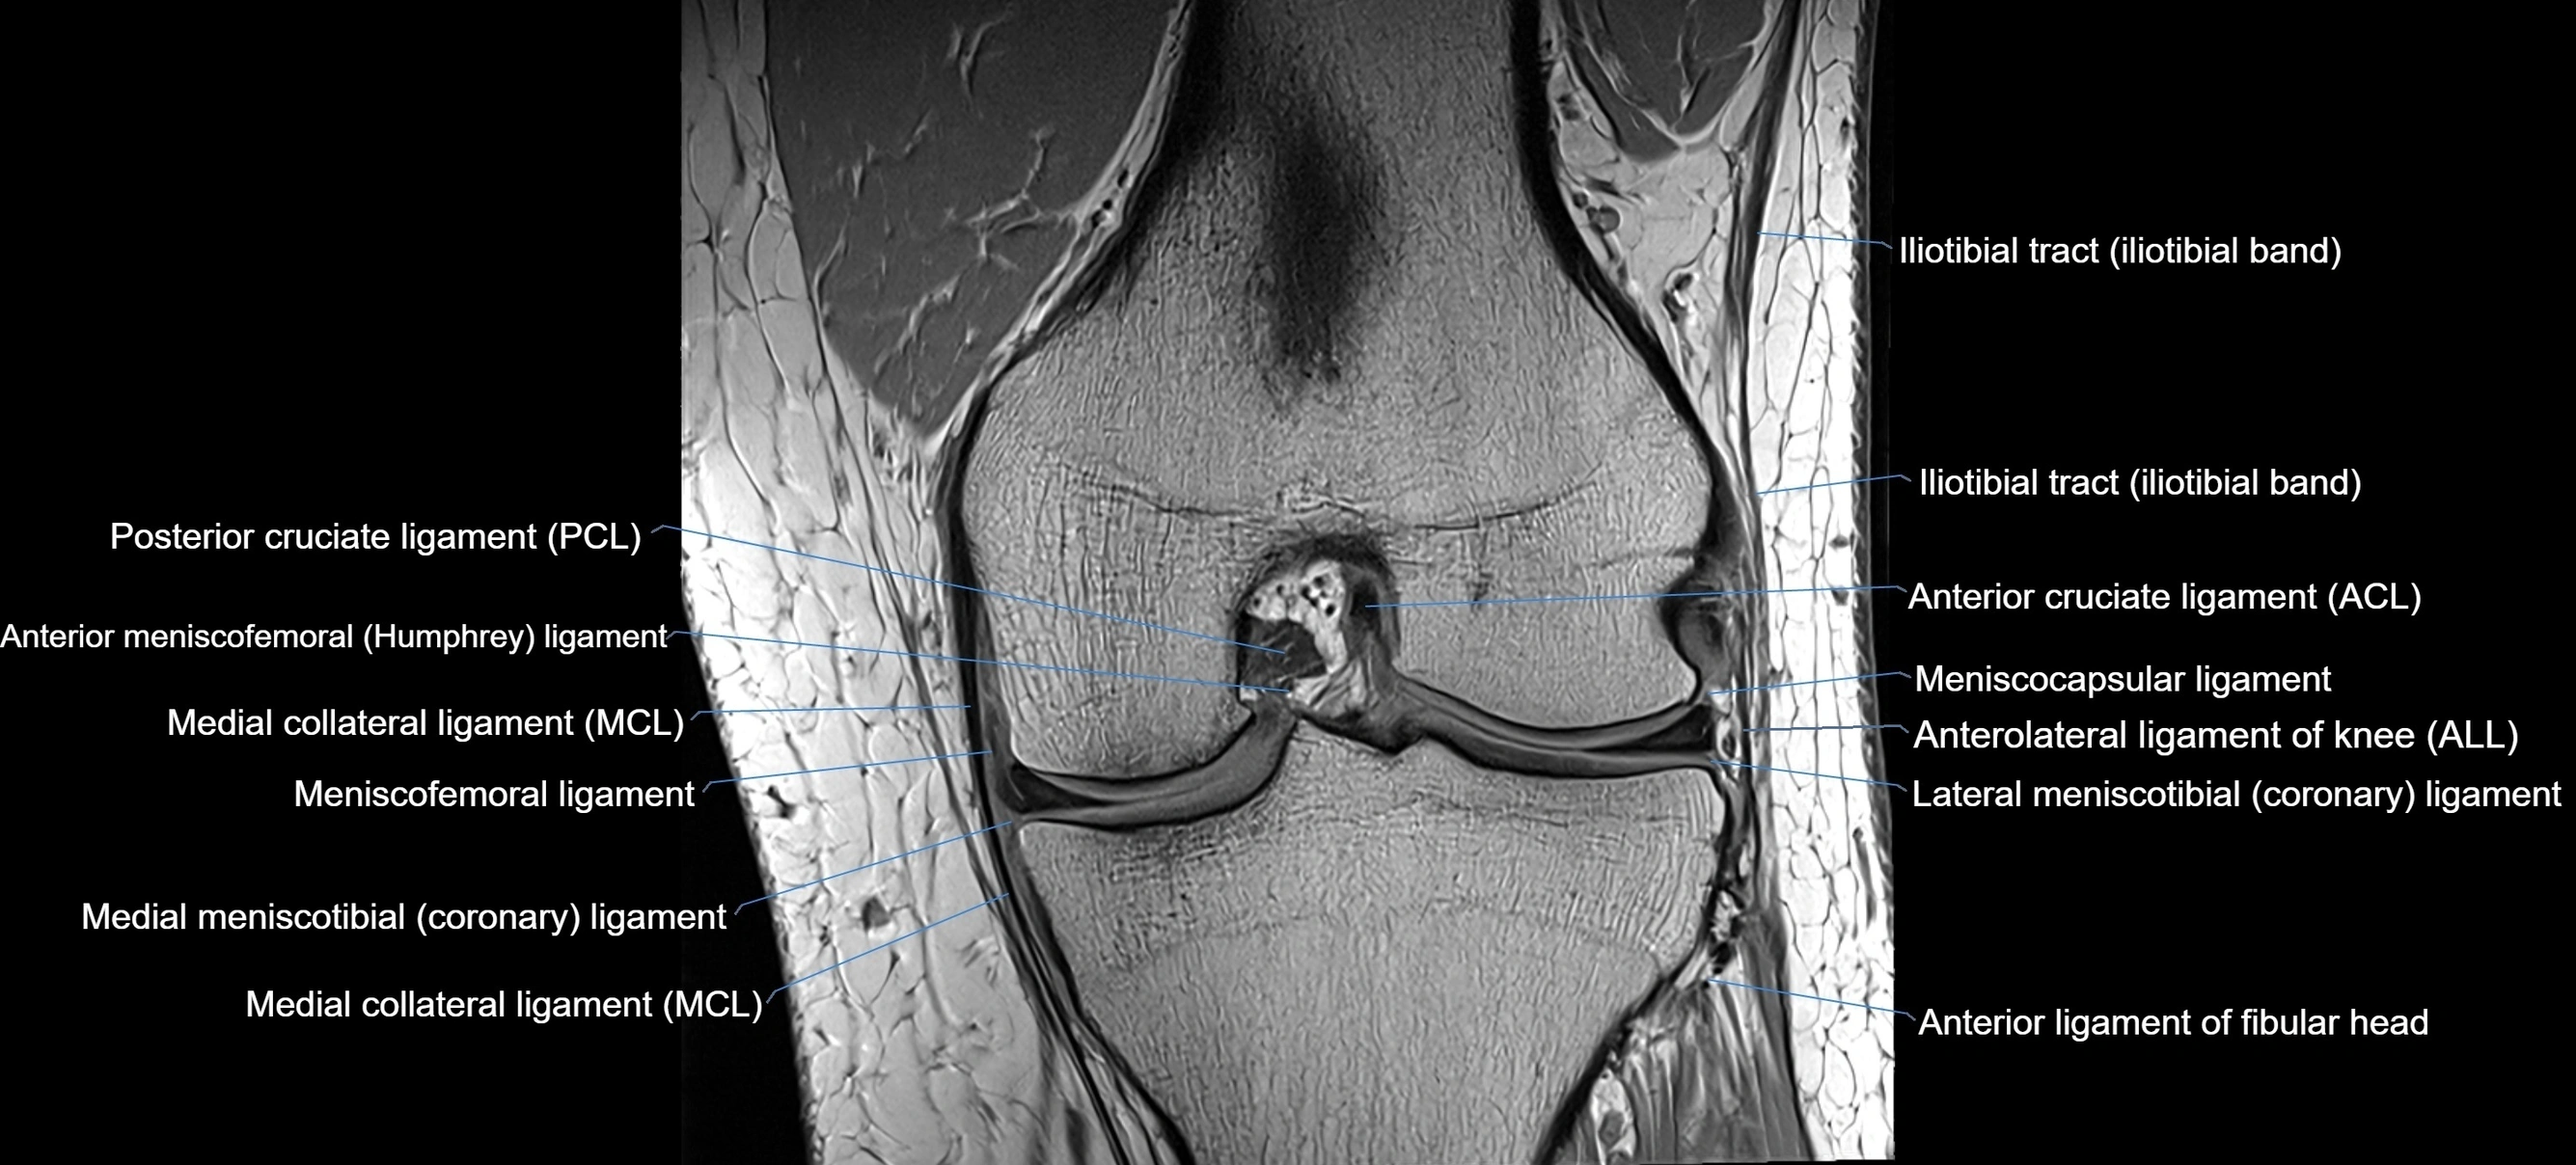

MRI images

image